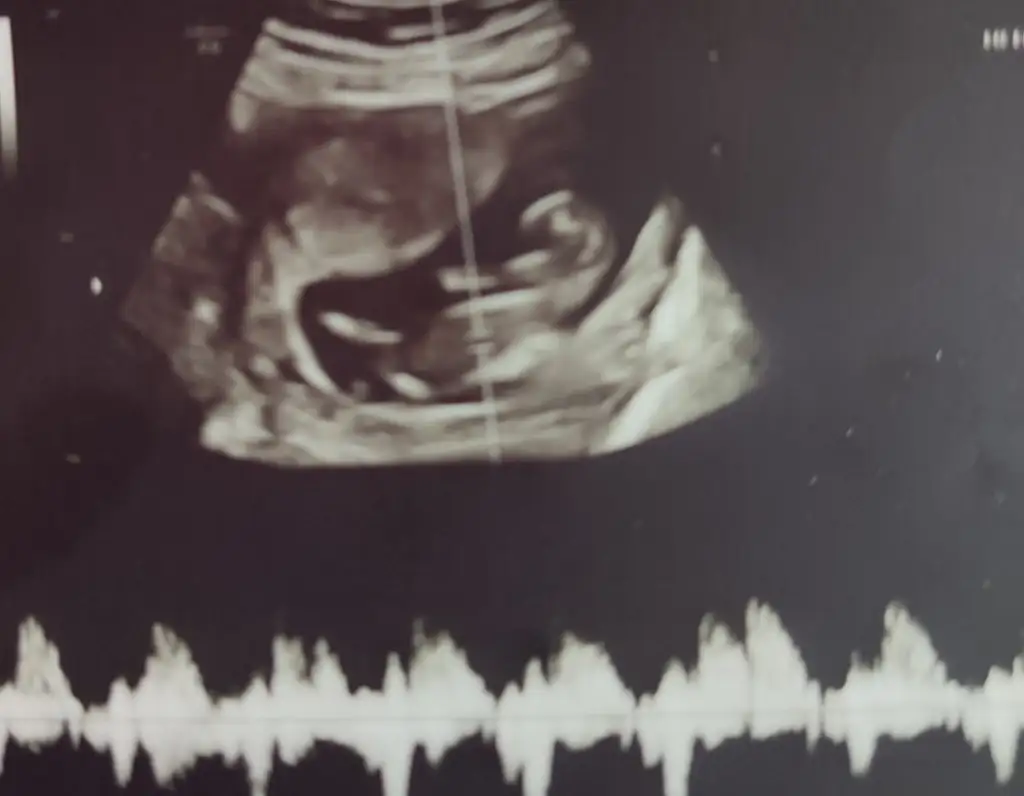

12+4 günlük hamileyim doktor %51 kıza benziyor ama birşey alma diğer

ay kesinleşir dedi ama merak ediyorum çok cinsiyet tahmini yaptırdim %70 kız dedi 1 kişi insatada diğer 2 kişi erkek dedi tahmini olan varmii

Ben de 12+3 iken gittim yani dün gittim belli değil cinsiyeti dedi ben çok merak ediyorum küçük bir tahminde de mi bulunamazsınız diyince %51 kıza benzettim dedi diğer kontrolüm tam 1 ay sonra anlamıyorum bu doktorları kafam karıştı daha bebeğe de hiçbir şey alamadım me yapsam da kesin öğrensem

Tahmininiz varmı hanımlar